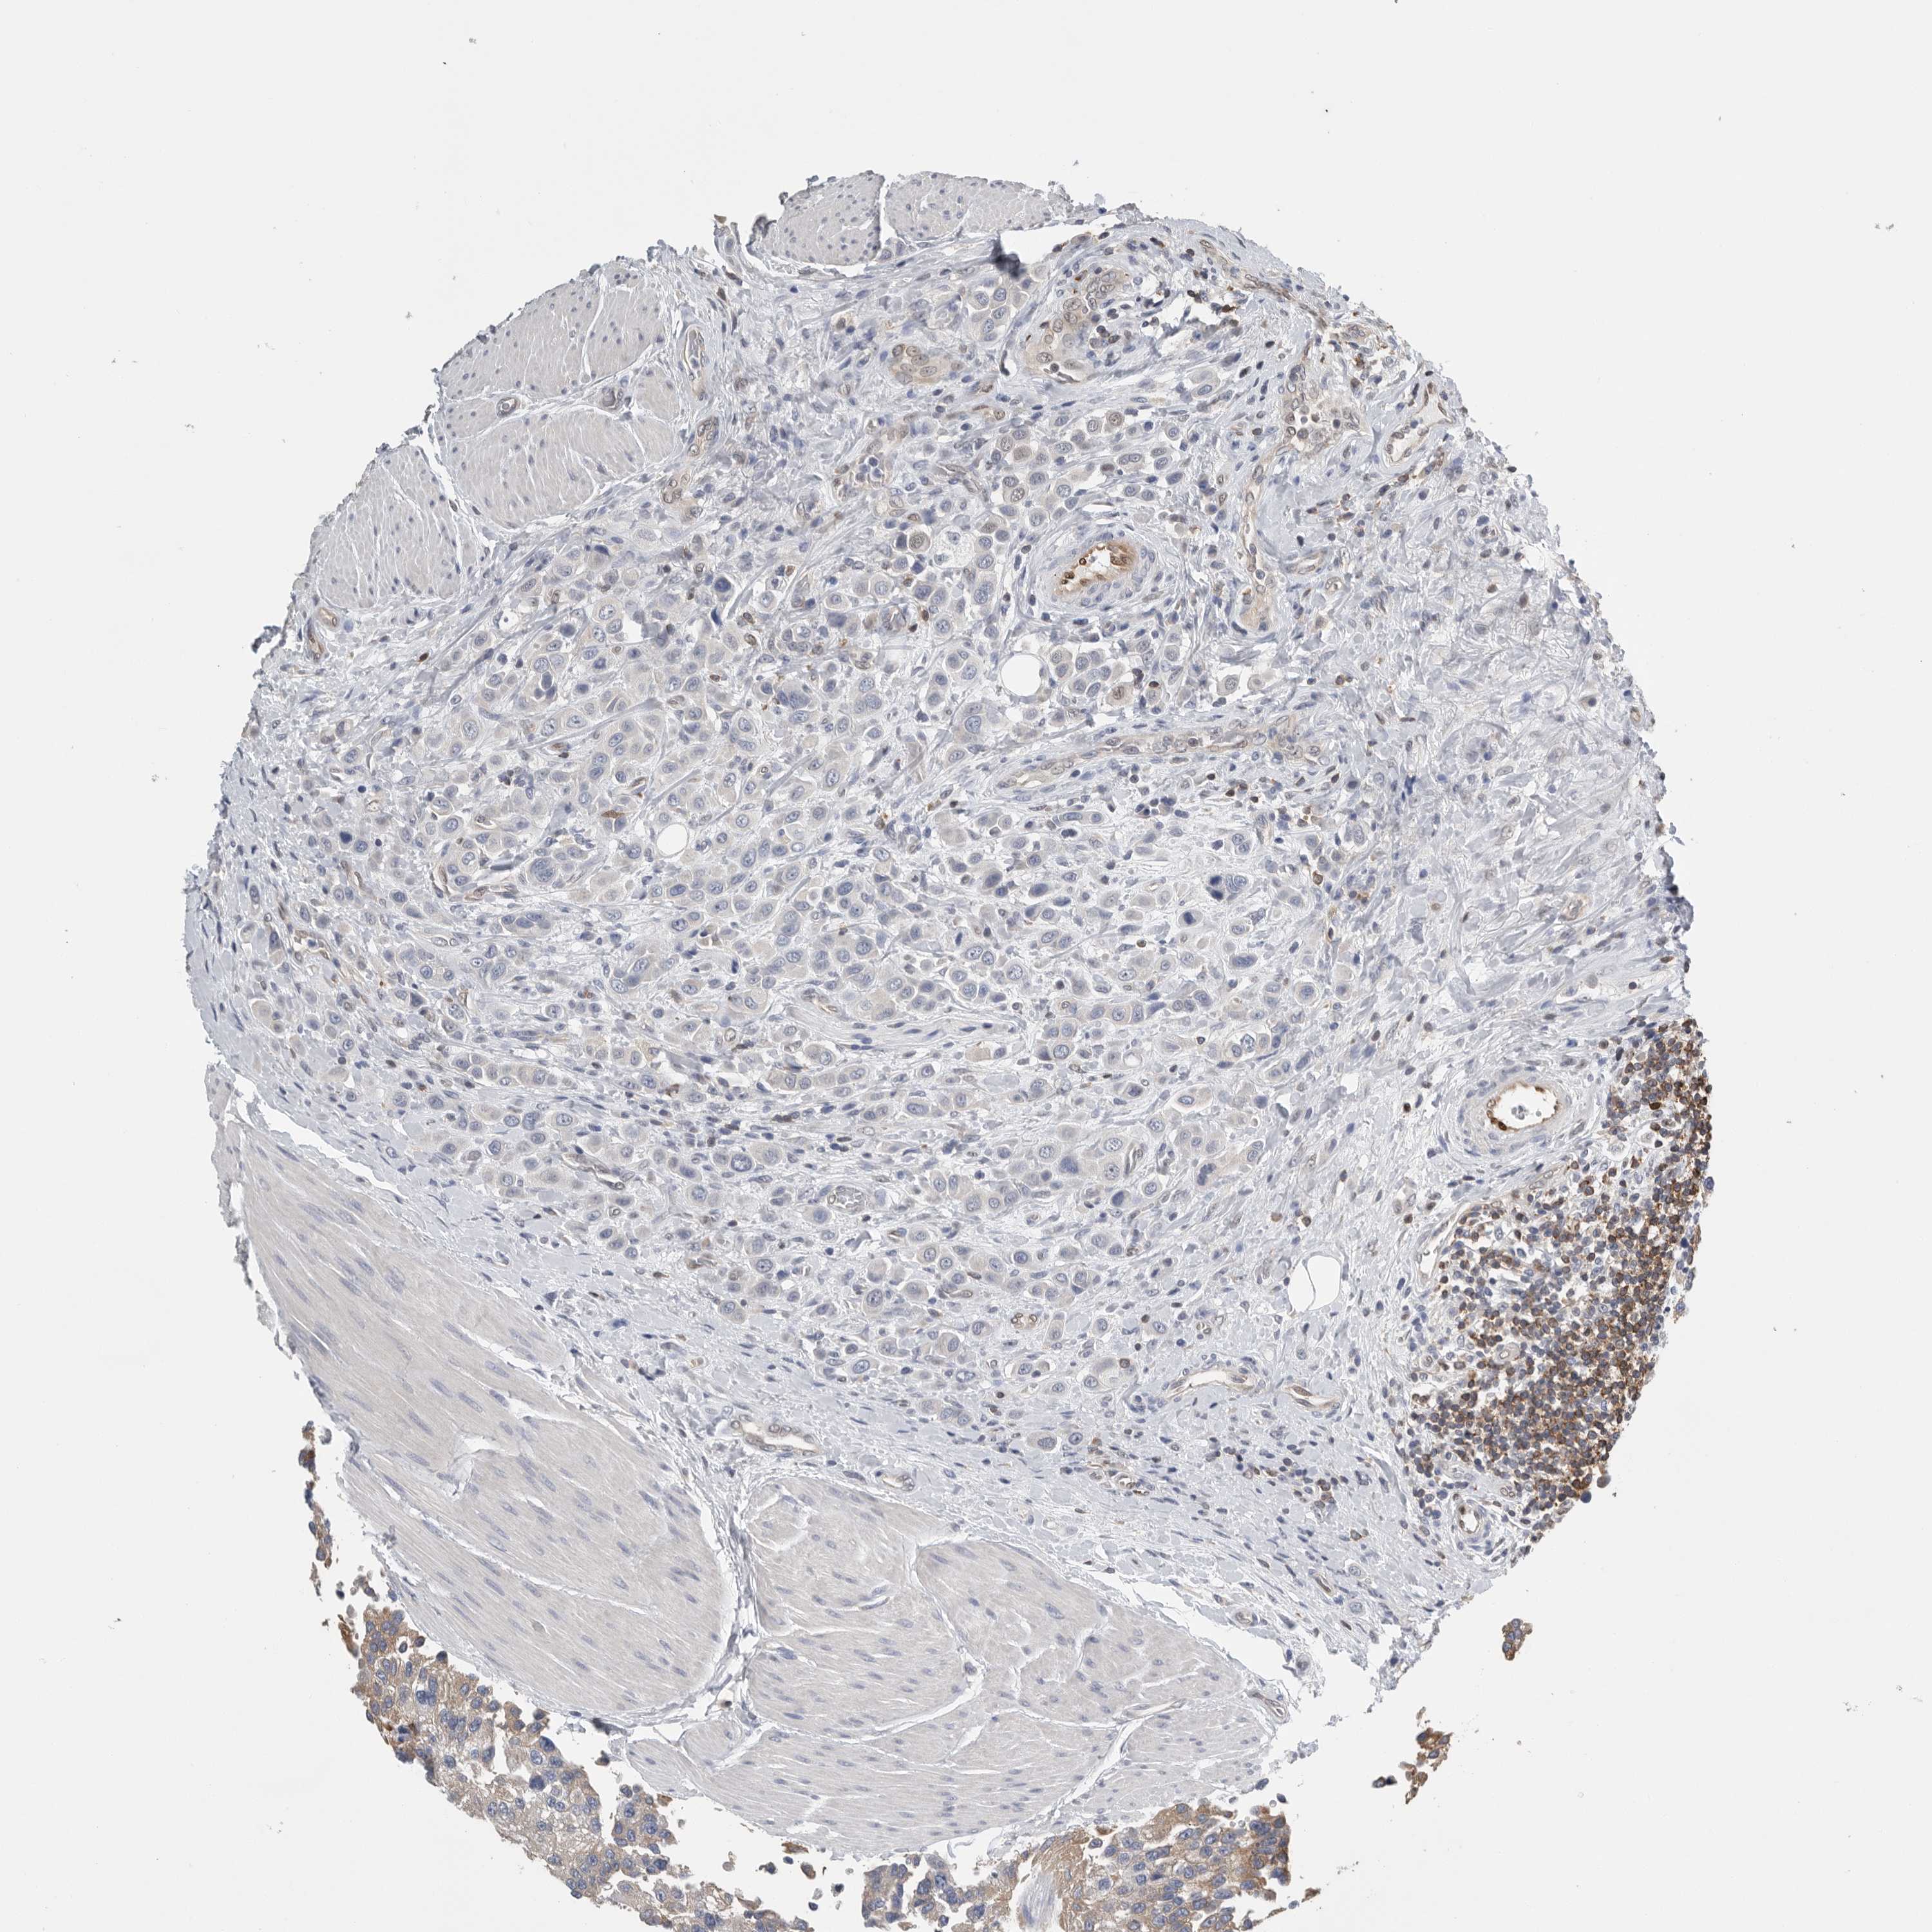

UROTHELIAL CANCER - Protein expressioni

A mouse-over function shows sample information and annotation data. Click on an image to view it in a full screen mode. Samples can be filtered based on level of antibody staining by selecting one or several of the following categories: high, medium, low and not detected. The assay and annotation is described here.

Antibody stainingi

Antibody staining in the annotated cell types in the current human tissue is reported as not detected, low, medium, or high, based on conventional immunohistochemistry profiling in selected tissues. This score is based on the combination of the staining intensity and fraction of stained cells.

Each image is clickable and will lead to virtual microscopy that enables deeper exploration of all samples and also displays staining intensity scores, fraction scores and subcellular localization as well as patient and tissue information for each sample.

Antibody HPA001032

Antibody HPA027214

Antibody CAB037024

Staining

High

Medium

Low

Not detected

Intensity

Strong

Moderate

Weak

Negative

Quantity

>75%

75%-25%

<25%

None

Location

Nuclear

Cytoplasmic/membranous

Cytoplasmic/membranous,nuclear

Urothelial carcinoma, High grade

Urothelial carcinoma, Low grade

Urothelial carcinoma, NOS